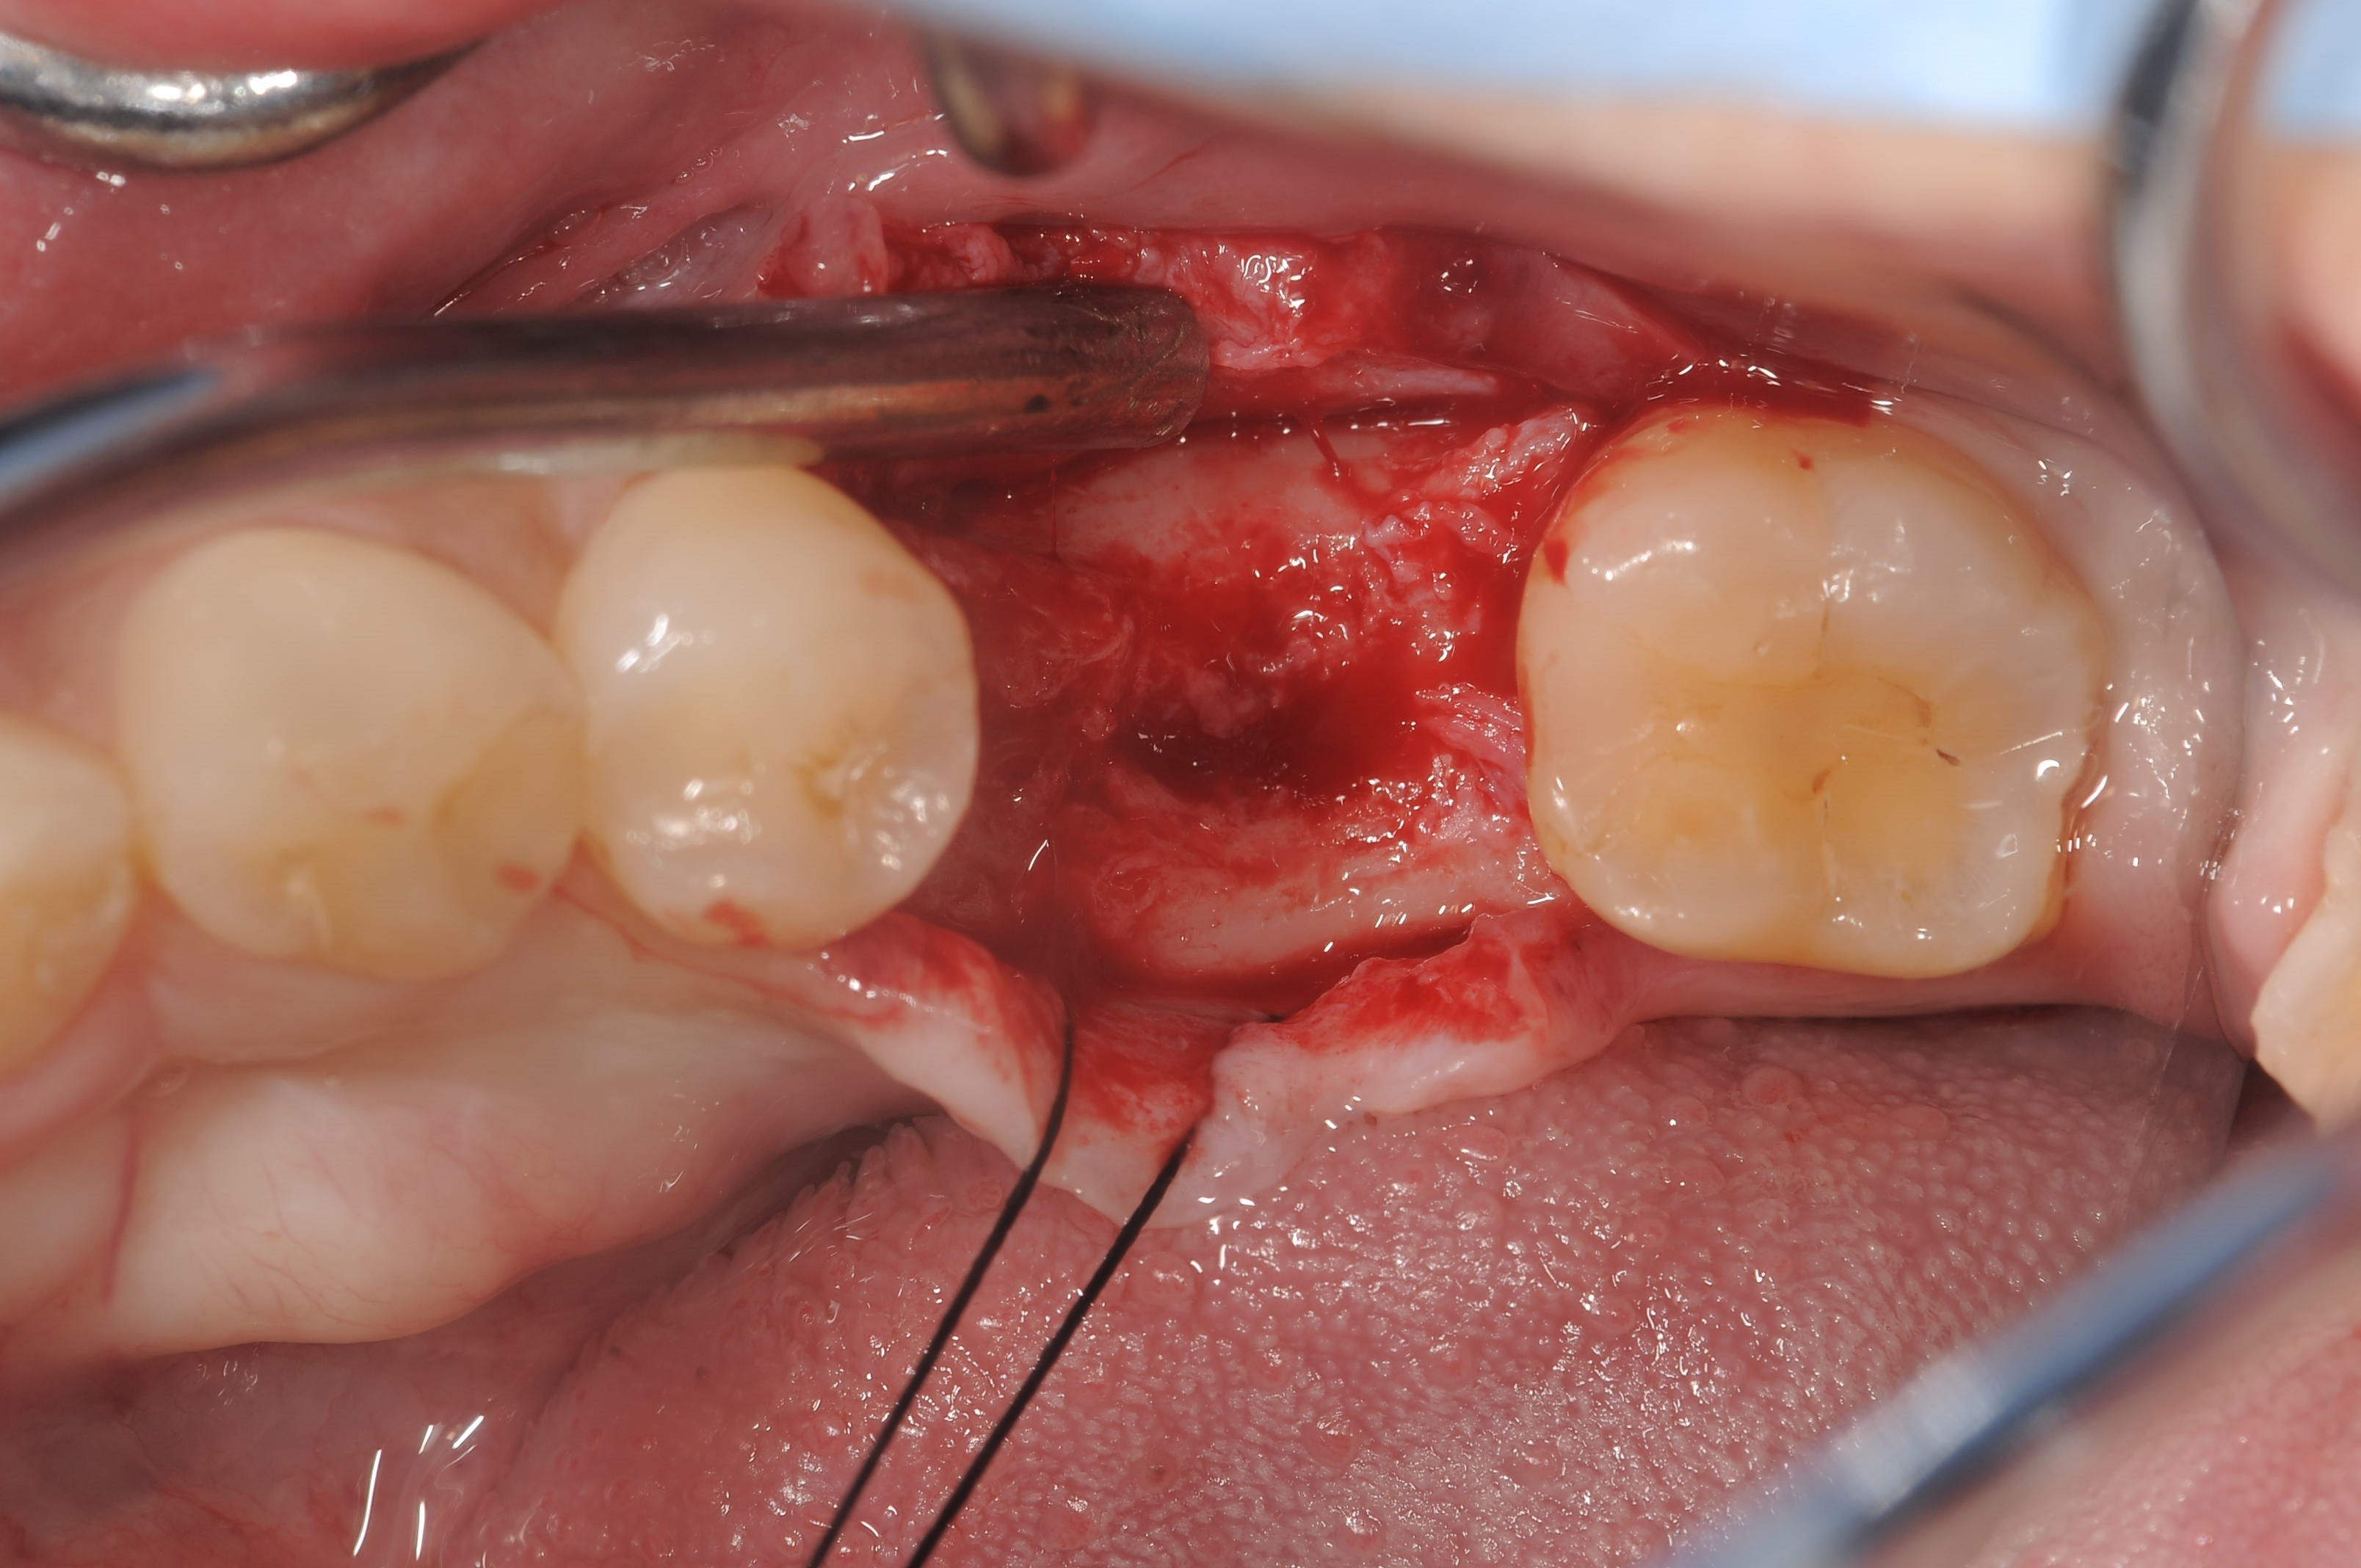

右下第一大臼歯部へストローマンボーンレベルRC4.8Φ×10mm埋入